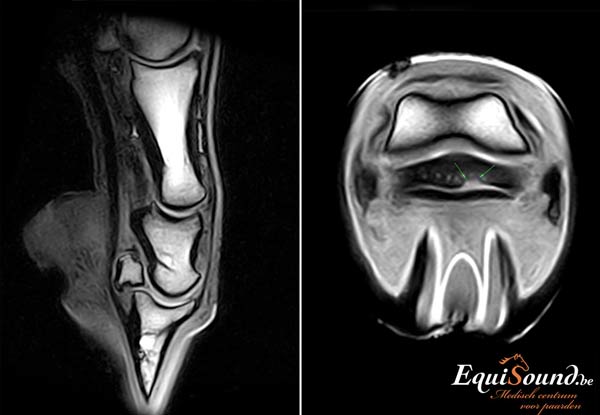

EquiSound beschikt over het eerste MRI-toestel in de Benelux dat het paard kan scannen van ondervoet tot de achterknie, inclusief het hoofd en de nek. Het is ook de eerste MRI-scanner ter wereld die een paard zowel rechtopstaand als liggend in beeld kan brengen. Geen enkel onderdeeltje van het paard, van ledematen tot hoofd, ontsnapt nog aan het oog van onze dierenartsen.

Een MRI-scanner is een geavanceerd toestel dat ons in staat stelt zowel de weke delen (ligamenten, pezen en kraakbeen) als het beenderstel van een paard in 3 dimensies te evalueren (3D). Dit is niet mogelijk met radiografie en echografie. Bovendien levert de technologie veel gedetailleerdere beelden af dan radiologie, echografie of CT. De interpretatie van de MRI-beelden wordt bij EquiSound ondersteund door ervaren MRI-specialisten Myra Barrett en Kurt Selberg vanuit de USA . Op die manier verzekert EquiSound topdiagnostiek bij uw paard vanaf het eerste uur.

Het hoogtechnologische toestel van EquiSound kan een paard zowel in een rechtstaande als liggende positie scannen. De ondervoet onderzoeken we bijvoorbeeld terwijl het paard recht blijft staan. Om bijvoorbeeld de achterknie te scannen, brengen we het paard dan weer even onder narcose (algemene anesthesie). Dit is noodzakelijk omdat het paard anders te veel beweegt. Elke opname neemt immers 3 tot 6 minuten in beslag. Van paarden onder algemene anesthesie kunnen we bovendien beelden maken met een hogere resolutie. Zo kan de prognose voor uw paard nog beter ingeschat worden. Een geassisteerde recovery zorgt ervoor dat het paard veilig ontwaakt.